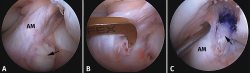

Los hallazgos de RM en las roturas parciales del LCA consisten en un aumento de la señal intrasustancial, defectos focales, distorsión y atenuación de fibras o una orientación anormal del ligamento(1,16)(Figuras 4 y 5). El diagnóstico es más sencillo en fase aguda, por la presencia de signos secundarios con edema y derrame articular. La principal dificultad diagnóstica con RM en la fase aguda consiste en diferenciar roturas parciales de alto grado de completas(1,16).

Figura 4. Rotura parcial del fascículo anteromedial (AM) del ligamento cruzado anterior (LCA) con formación de pequeño ganglión en la escotadura intercondílea. Corte oblicuo coronal (A) y axial (B) de resonancia magnética (RM) potenciados en densidad protónica con supresión grasa que muestran una rotura del fascículo AM (flechas). Fascículo posterolateral normal (cabezas de flecha).

Figura 5. Rotura parcial del fascículo posterolateral (PL) del ligamento cruzado anterior (LCA). Corte oblicuo coronal (A) y axial (B) de resonancia magnética (RM) potenciados en densidad protónica con supresión grasa que muestran una rotura completa proximal del fascículo PL (flechas). Fascículo anteromedial normal (cabezas de flecha).

Figura 7. Rotura parcial del fascículo anteromedial (AM). A: esquema que ilustra una rotura parcial del ligamento cruzado anterior (LCA) afectando al fascículo AM; B: imagen artroscópica de la rodilla izquierda desde el portal anterolateral. Rotura completa del fascículo AM (flecha) con un fascículo posterolateral (PL) intacto y tenso a la exploración con el palpador.

Sin embargo, a pesar de estos esfuerzos, la valoración de la actitud terapéutica no se basa en los hallazgos de RM. Si bien la valoración combinada de la exploración clínica y los hallazgos de RM permite establecer una sospecha de inestabilidad en una lesión parcial del LCA, la exploración bajo anestesia con la maniobra de pivot shift sigue siendo el test más fiable en la valoración funcional del LCA y el tratamiento quirúrgico definitivo se debe basar en la exploración artroscópica(17)(Figuras 7 y 8).

Figura 8. Rotura parcial del fascículo posterolateral (PL). A: esquema que ilustra una rotura parcial del ligamento cruzado anterior (LCA) afectando al fascículo PL; B: visión artroscópica de la rodilla derecha desde el portal anterolateral. Se observa una rotura completa del fascículo PL (flecha), tras la separación con el palpador del fascículo anteromedial (AM).